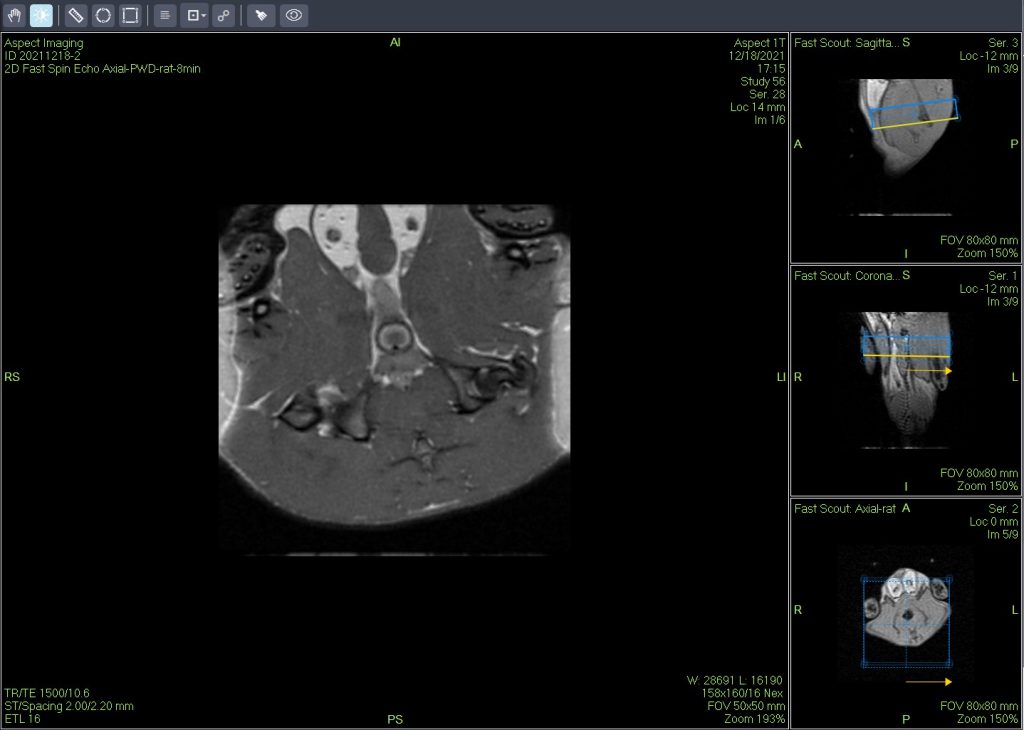

活体磁共振成像在模型小鼠中检测到局灶性肝损伤(图A)。肝脏的高分辨率离体MRH评估可以在小鼠(图B和C)中鉴定几个单独的局灶性脂肪病变。通过常规组织病理学证实病变为局灶性脂肪改变(图C)。